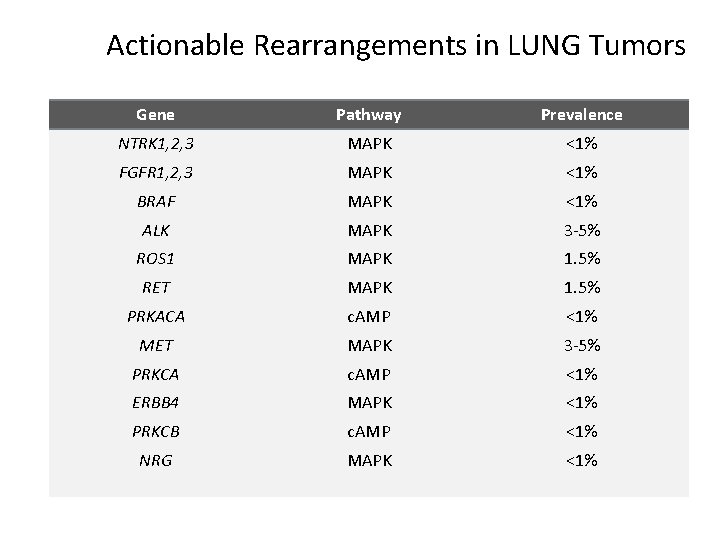

Actionable Rearrangements in LUNG Tumors Gene Pathway Prevalence NTRK 1, 2, 3 MAPK <1% FGFR 1, 2, 3 MAPK <1% BRAF MAPK <1% ALK MAPK 3 -5% ROS 1 MAPK 1. 5% RET MAPK 1. 5% PRKACA c. AMP <1% MET MAPK 3 -5% PRKCA c. AMP <1% ERBB 4 MAPK <1% PRKCB c. AMP <1% NRG MAPK <1%